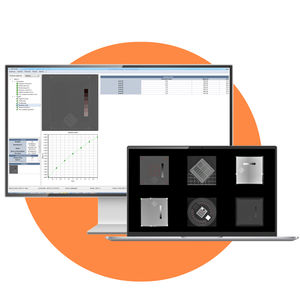

... Para satisfacer las necesidades de control de calidad de las imágenes radiológicas, ofrecemos el paquete RADIO QA. Modalidades DICOM compatibles: CR (Radiografía computarizada), DX (Radiografía digital), RF (Fluoroscopia), XA (Angiografía ...

AQUILAB

... DENSITY QA Pack Módulos para el análisis automático de imágenes DICOM adquiridas con diversos objetos de prueba dedicados para el control de densidad Principales parámetros medidos Para cada inserto presente en el fantoma, ...

AQUILAB